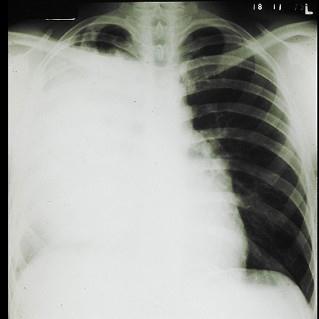

问题 男,62岁,刺激性咳嗽,痰血2个月,近两周来呼吸困难,半年前体检X线胸片未见明显异常。查体:气管右移,右胸廓下陷,叩实,可闻管状呼吸音,心界右移。X线胸片如图所示: 假设:确诊后首选的治疗方案 ( )

选项 A、化学治疗 B、放射治疗 C、口服利福平,异烟肼 D、开胸探查,肺切除 E、大剂量青霉素及链霉素治疗

答案 D